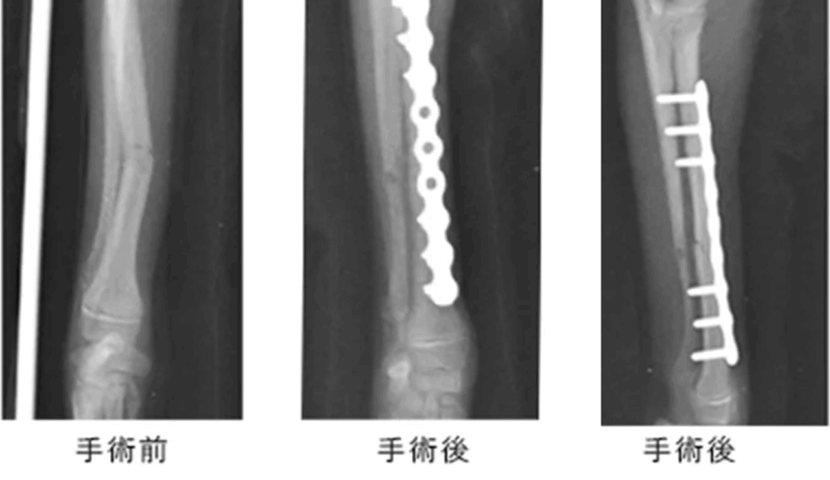

トイ・プードル 3歳

落とした後から前肢を挙上している

右前肢の完全挙上

| 小型犬は前肢の骨が非常に細いため、高いところから着地しただけで手首に近い部分の前肢の骨が折れてしまいます。そして手首付近の骨は筋肉に覆われていないため、治癒しにくく、再骨折もしやすいために正確な手術が求められます。 当院では、固定力の強いロッキングコンプレッションプレート(LCP)という強力なプレートを使用しています。またそれでも固定力が不十分の場合は、創外固定法を併用することもあります。 |